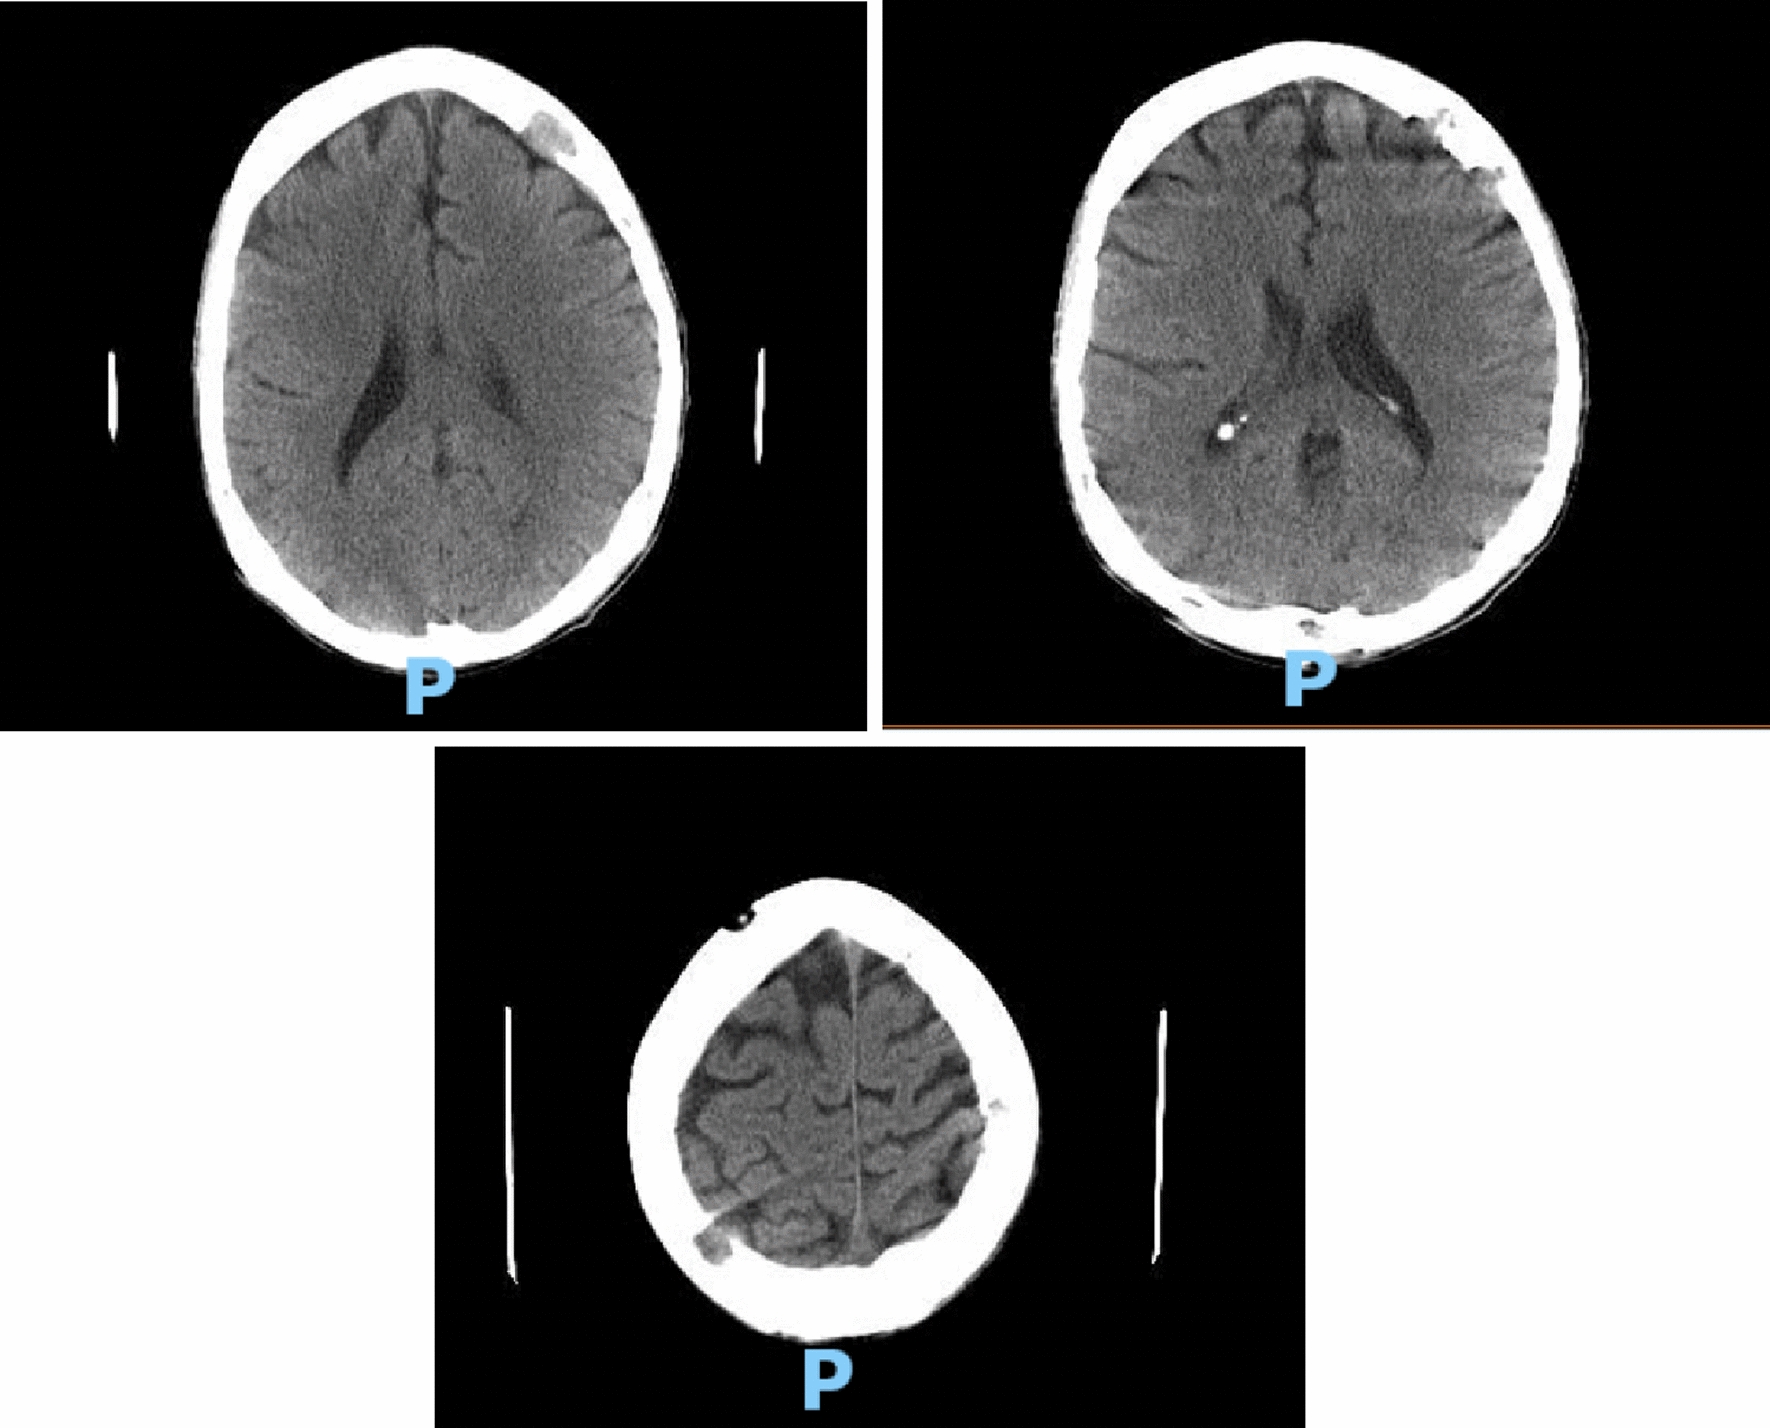

Hematology workup revealed mild leukocytosis (10.94 K/uL), normocytic anemia (hemoglobin 7.3 g/dL, mean corpuscular volume 94.4fL), and thrombocytosis (platelet count 901,000). Comprehensive metabolic panel was consistent with acute kidney injury (AKI) (creatinine 3 mg/dL, blood urea nitrogen 45 mg/dL—baseline unknown), tumor lysis syndrome (potassium 6.3 mmol/L, uric acid 21.7 mg/dL, phosphorus 5.6 mg/dL, and calcium 8 mg/dL). hyponatremia at 127 mmol/L, high anion gap metabolic acidosis (bicarbonate level 6, pH 7.23 on VBG, lactate 11.5), lactate dehydrogenase > 25,000 units/L, and elevated transaminases in a mixed pattern. Chest x-ray showed an ill-defined erosive mass of the left 4th to 5th lateral ribs, a thyroid mass, and trace pleural effusions (Fig. 1). Computerized tomography (CT) chest, abdomen, and pelvis had several significant findings pointing towards widespread malignancy. It showed a left supra-clavicular nodal mass measuring 5.4 × 4 × 3.6 cm, diffusely heterogeneous liver possibly reflecting metastatic disease, nodular soft tissue densities along with the hepatic capsule suspicious for hepatic capsular implants, large volume abdominopelvic ascites with extensive peritoneal soft tissue thickening/omental caking compatible with peritoneal carcinomatosis, mass-like thickening of the rectum, numerous lytic lesions involving the bilateral scapula, multiple ribs, bilateral proximal humerus, numerous vertebral bodies, pelvic bones, and proximal femur (Fig. 2). CT Head showed numerous diffuse lytic calvarial lesions concerning metastatic disease, but no mass effect was seen (Fig. 3).

Fig. 3.

Multiple lytic lesions all over the extent of the calvarium